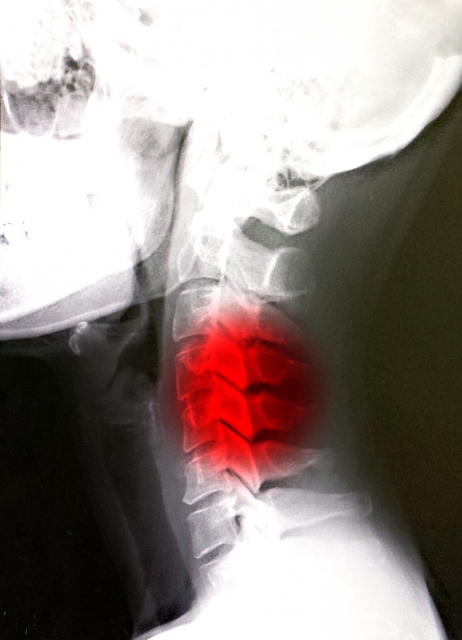

その中でも特に多いのが「むち打ち(頚椎捻挫)」です。

レントゲンなどの検査を受け、診断をもらいます。

むち打ちは首だけの問題ではありません。

骨格・筋肉・神経のバランスを整え、根本から回復へ導きます。